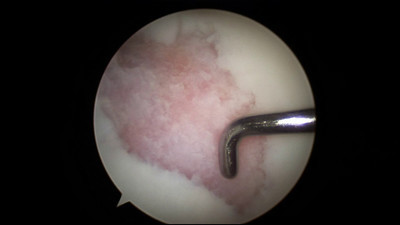

Introduction Spectrum of disease entities from single, focal defects to advanced degenerative disease of articular (hyaline) cartilage Epidemiology incidence 5-10% of people > 40 years old have high grade chondral lesions location chronic ACL tear anterior aspect of lateral femoral chondyle and posterolateral tibial plateau osteochondritis dissecans 70% of lesions found in posterolateral aspect of medial femoral condyle Pathophysiology mechanism of injury acute trauma or chronic repetitive overload impaction resulting in cartilage softening; fissuring; flap tears; or delamination the cause of OCD is unknown pathomechanics impaction forces greater than 24 MPa will disrupt normal cartilage cellular biology cartilage injuries have limited spontaneous healing and propensity to worsen over time Anatomy See Articular Cartilage Basic Science Classification Outerbridge Arthroscopic Grading System Grade 0 Normal cartilage Grade I Softening and swelling Grade II Superficial fissures Grade III Deep fissures, without exposed bone Grade IV Exposed subchondral bone ICRS (International Cartilage Repair Society) Grading System Grade 0 Normal cartilage Grade 1 Nearly normal (superficial lesions) Grade 2 Abnormal (lesions extend < 50% of cartilage depth) Grade 3 Severely abnormal (>50% of cartilage depth) Grade 4 Severely abnormal (through the subchondral bone) Presentation History commonly present with history of precipitating trauma some defects found incidentally on MRI or arthroscopy Symptoms asymptomatic vs. localized knee pain may complain of effusion, motion deficits, mechanical symptoms (e.g., catching, instability) Physical exam inspection look for background factors that predispose to the formation of articular defects joint laxity malalignment compartment overload motion assess range of motion, ligamentous stability, gait Imaging Radiographs indications used to rule out arthritis, bony defects, and check alignment recommended views standing AP, lateral, merchant views optional views semiflexed 45 deg PA views most sensitive for early joint space narrowing long-leg alignment views determine the mechanical axis CT scan indications better evaluation of bone loss findings used to measure TT-TG when evaluating the patello-femoral joint MRI indication most sensitive for evaluating focal defects views Fat-suppressed T2, proton density, T2 fast spin-echo (FSE) offer improved sensitivity and specificity over standard sequences dGEMRIC (delayed gadolinium-enhanced MRI for cartilage) and T2-mapping are evolving techniques to evaluate cartilage defects and repair Studies Laboratory may be used to rule out inflammatory disease Treatment Nonoperative rest, NSAIDs, physiotherapy, weight loss indications first line of treatment when symptoms are mild viscosupplementatoin, corticosteroid injections, unloader brace indications controversial may provide symptomatic relief but healing of defect is unlikely Operative debridement/chondroplasty vs. reconstruction techniques indications failure of nonoperative management acute osteochondral fractures resulting in full-thickness loss of cartilage technique treatment is individualized, there is no one best technique for all defects decision-making algorithm is based on several factors patient factors age skeletal maturity low vs. high demand activities ability to tolerate extended rehabilitation defect factors size of defect location contained vs. uncontained presence or absence of subchondral bone involvement basic algorithm (may vary depending on published data) femoral condyle defect correct malaligment, ligament instability, meniscal deficiency measure size < 4 cm2 = microfracture or osteochondral autograft transfer (pallative if older/low demand) > 4 cm2 = osteochondral allograft transplantation or autologous chondrocyte implantation patellofemoral defect address patellofemoral maltracking and malalignment measure size < 4 cm2 = microfracture or osteochondral autograft transfer > 4 cm2 = autologous chondrocyte implantation (microfracture if older/low demand) Surgical Techniques Debridement / Chondroplasty overview goal is to debride loose flaps of cartilage removal of loose chondral fragments may relieve mechanical symptoms short-term benefit in 50-70% of patients benefits include simple arthroscopic procedure, faster rehabilitation limitations problem is exposed subchondral bone or layers of injured cartilage unknown natural history of progression after treatment Fixation of Unstable Fragments overview need osteochondral fragment with adequate subchondral bone technique debride underlying nonviable tissue consider drilling subchondral bone or adding local bone graft fix with absorbable or nonabsorbable screws or devices benefits best results for unstable osteochondritis dissecans (OCD) fragments in patients with open physis limitations lower healing rates in skeletally mature patients nonabsorbable fixation (headless screws) should be removed at 3-6 months Marrow Stimulation Techniques overview goal is to allow access of marrow elements into defect to stimulate the formation of reparative tissue includes microfracture, abrasion chondroplasty, osteochondral drilling microfracture technique defect is prepared with stable vertical walls and the calcified cartilage layer is removed awls are used to make multiple perforations through the subchondral bone 3 - 4 mm apart protected weight bearing and continuous passive motion (CPM) are used while mesenchymal stem cells mature into mainly fibrocartilage benefits include cost-effectiveness, single-stage, arthroscopic best results for acute, contained cartilage lesions less than 2 cm x 2cm limitations poor results for larger defects >2 cm x 2cm does not address bone defects requires limitation of weight bearing for 6 - 8 weeks Osteochondral autograft / Mosaicplasty overview goal is to replace a cartilage defect in a high weight bearing area with normal autologous cartilage and bone plug(s) from a lower weight bearing area chondrocytes remain viable, bone graft is incorporated into subchondral bone and overlying cartilage layer heals. technique a recipient socket is drilled at the site of the defect a single or multiple small cylinders of normal articular cartilage with underlying bone are cored out from lesser weight bearing areas (periphery of trochlea or notch) plugs are then press-fit into the defect limitations size constraints and donor site morbidity limit usage of this technique matching the size and radius of curvature of cartilage defect is difficult fixation strength of graft initially decreases with initial healing response weight bearing should be delayed 3 months benefits include autologous tissue, cost-effectiveness, single-stage, may be performed arthroscopically Osteochondral allograft transplantation overview goal is to replace cartilage defect with live chondrocytes in mature matrix along with underlying bone fresh, refrigerated grafts are used which retain chondrocyte viability may be performed as a bulk graft (fixed with screws) or shell (dowels) grafts technique match the size and radius of curvature of articular cartilage with donor tissue a recipient socket is drilled at the site of the defect an osteochondral dowel of the appropriate size is cored out of the donor the dowel is press-fit into place benefits include ability to address larger defects, can correct significant bone loss, useful in revision of other techniques limitations limited availability and high cost of donor tissue live allograft tissue carries potential risk of infection Autologous chondrocyte implantation (ACI) overview cell therapy with goal of forming autologous "hyaline-like" cartilage technique arthroscopic harvest of cartilage from a lesser weight bearing area in the lab, chondrocytes are released from matrix and are expanded in culture defect is prepared, and chondrocytes are then injected under a periosteal patch sewn over the defect during a second surgery benefits may provide better histologic tissue than marrow stimulation long term results comparable to microfracture in most series include regeneration of autologous tissue, can address larger defects limitations must have full-thickness cartilage margins around the defect open surgery 2-stage procedure prolonged protection necessary to allow for maturation Patellar cartilage unloading procedures Maquet (tibia tubercle anteriorization) indicated only for distal pole lesions only elevate 1 cm or else risk of skin necrosis contraindications superior patellar arthrosis (scope before you perform the surgery) Fulkerson alignment surgery (tibia tubercle anteriorization and medialization indications (controversial) lateral and distal pole lesions increased Q angle contraindications superior medial patellar arthrosis (scope before you perform the surgery) skeletal immaturity Matrix-associated autologous chondrocyte implantation overview example is "MACI" cells are cultured and embedded in a matrix or scaffold matrix is secured with fibrin glue or sutures benefits only FDA approved cell therapy for cartilage in the USA include ability to perform without suturing, may be performed arthroscopically limitations 2-stage procedure Expense

QUESTIONS 1 of 10 1 2 3 4 5 6 7 8 9 10 Previous Next Sorry, this question is for PEAK Premium Subscribers only Upgrade to PEAK Sorry, this question is for PEAK Premium Subscribers only Upgrade to PEAK Sorry, this question is for PEAK Premium Subscribers only Upgrade to PEAK Sorry, this question is for PEAK Premium Subscribers only Upgrade to PEAK (OBQ13.203) What type of tissue is formed by the activation of marrow mesenchymal cells following subchondral drilling of an 8x7 mm osteochondral defect? Review Topic QID: 4838 1 Elastic cartilage 0% (8/4288) 2 Fibrocartilage 96% (4121/4288) 3 Hyaline cartilage 1% (58/4288) 4 Trabecular bone 1% (33/4288) 5 Hypertrophic chondrocytes 1% (51/4288) ML 1 Select Answer to see Preferred Response PREFERRED RESPONSE 2 (OBQ10.257) Following a medial femoral condyle osteochondral autograft mosaicplasty, which of the following statements best describes the fixation of the graft? Review Topic QID: 3353 1 Graft fixation strength increases linearly with time until subchondral union at 3 months 5% (66/1215) 2 Graft fixation strength initially decreases during the early healing phase, and then increases with subchondral bone healing 86% (1041/1215) 3 Graft fixation strength does not change during the first 3 months following surgery 2% (20/1215) 4 Graft fixation strength is enhanced by early weight bearing 3% (42/1215) 5 Graft fixation strength initially increases over the first 6 weeks, then recedes with bony remodeling 4% (45/1215) ML 1 Select Answer to see Preferred Response PREFERRED RESPONSE 2 (OBQ11.1) A 24-year-old female has moderate arthrosis of the medial facet of the patella and the medial femoral condyle. Which of the following procedures is contraindicated? Review Topic QID: 3424 1 Anterior (Maquet) tibial tubercle osteotomy 4% (161/3819) 2 Anteromedial (Fulkerson) tibial tubercle osteotomy 76% (2903/3819) 3 Anterolateral tibial tubercle osteotomy 10% (366/3819) 4 Medial opening wedge high tibial osteotomy 6% (220/3819) 5 Lateral closing wedge high tibial osteotomy 4% (149/3819) ML 2 Select Answer to see Preferred Response PREFERRED RESPONSE 2 (SBQ07SM.32) A patient with a symptomatic chondral defect undergoes the arthroscopic procedure seen in Figure A. The reparative tissue would best be described as which of the following? Review Topic QID: 1417 FIGURES: A 1 Fibrocartilage 94% (959/1016) 2 Fibrous tissue 2% (19/1016) 3 Elastofibroma 0% (2/1016) 4 Hyaline cartilage 3% (27/1016) 5 Chondromalacia 0% (5/1016) ML 1 Select Answer to see Preferred Response PREFERRED RESPONSE 1 (OBQ08.94) A 32-year-old female is referred to you for definitive treatment of a symptomatic focal chondral defect on her medial femoral condyle. A photograph from a recent diagnostic arthroscopy shows the defect (Figure A), which measured 25 x 25mm after debridement. What surgical treatment would you recommend? Review Topic QID: 480 FIGURES: A 1 Osteochondral autograft with 1-2 plugs 27% (119/434) 2 Osteochondral allograft 49% (213/434) 3 Microfracture 20% (86/434) 4 Unicompartment arthoplasty 3% (11/434) 5 Abrasion arthroplasty 0% (1/434) ML 4 Select Answer to see Preferred Response PREFERRED RESPONSE 2 (OBQ06.186) All of the following are acceptable scenarios for the use of autologous chondrocyte implantation (ACI) in the patellofemoral joint EXCEPT: Review Topic QID: 372 1 Grade 4 lesion of the medial femoral condyle 10% (186/1838) 2 Grade 4 lesion of the trochlea 6% (110/1838) 3 Joint space narrowing on Merchant view 57% (1040/1838) 4 Varus mechanical axis on standing full length radiograph 23% (417/1838) 5 Concomitant anteromedial tibial tubercle transfer osteotomy (Fulkerson's) 5% (83/1838) ML 4 Select Answer to see Preferred Response PREFERRED RESPONSE 3